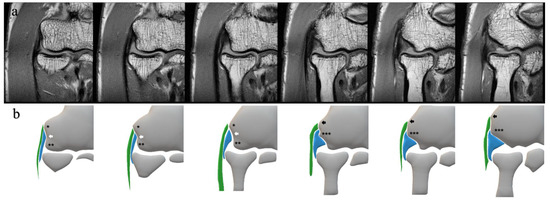

2.2. MRI Protocol and Definition of the Structures

2.3. MRI Scoring and Evaluation